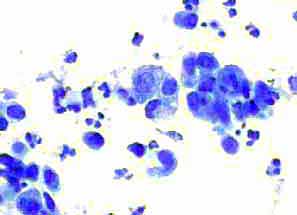

Aσθενής 45 ετών, με γνωστή παρουσία πολλαπλών κύστεων και στους δύο μαστούς εδώ και πολλά χρόνια.. Επώδυνη κύστη διαμέτρου 4 εκ. στον αριστερό μαστό. Κάτω από υπερηχογραφικό έλεγχο παρακέντηση και αφαίρεση περίπου 20 κ. εκ. κιτρινωπού υγρού.

Kύτταρα τοιχώματος κύστης μαστού. Αφρώδη κύτταρα, άφθονα πολυμορφοπύρηνα

Άμεση χρώση στεγνών παρασκευασμάτων, χωρίς μονιμοποίηση, κατά Papanicolaou και με  bleu de methylen.